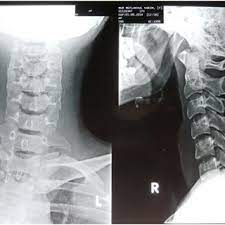

Diagnostic Imaging Pathways Cervical Spine Injury from dbwmpns0f8ewg.cloudfront.net Enter search terms and tap the search button. Please understand that our phone lines must be clear for urg. Here's what to expect with this painless procedure and why your dentist may recommend it. This procedure may be used to diagnose back or neck pain, fractures or broken bones, arthritis, degeneration of the disks, tumors, or other problems. It's commonly done after someone has been in an automobile or other accident. They show pictures of your internal tissues, bones, and organs.

This procedure may be used to diagnose back or neck pain, fractures or broken bones, arthritis, degeneration of the disks, tumors, or other problems. Enter search terms and tap the search button. They show pictures of your internal tissues, bones, and organs. Please understand that our phone lines must be clear for urg. Here's what to expect with this painless procedure and why your dentist may recommend it.